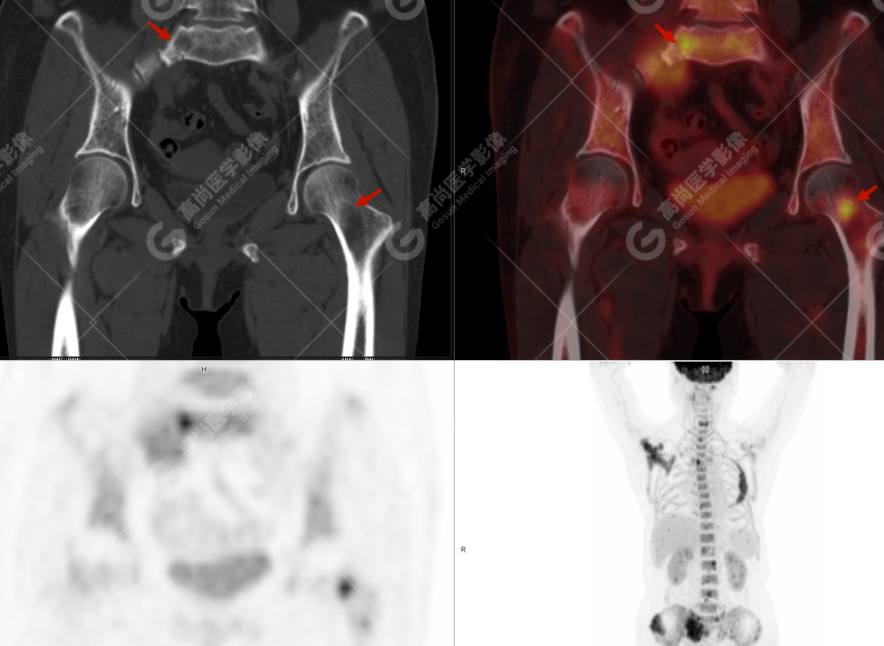

患者,女性,64 岁,因腰痛伴双下肢放射痛 3 月就诊,外院 CT 提示:左侧第四肋骨、右侧肩胛骨及颈 1、6 椎体骨质破坏,考虑转移;于本中心 PET-CT 协诊。既往史:剖宫产;否认外伤史,否认过敏史,否认家族肿瘤史。

颅骨、寰椎前弓左侧份、第 6 颈椎、双侧肩胛骨(右侧为著)、左侧第 4 肋骨、第 1 胸椎、第 4 胸椎、第 2 腰椎及附件、第 4 腰椎及附件、骶骨、右侧髂骨、左侧坐骨结节、左侧股骨颈、双侧股骨小转子等均不同程度骨质吸收、破坏,其中右侧肩胛骨、左侧第 4 肋骨及骶骨右侧份软组织肿块影形成,上述病变均考虑恶性肿瘤(血液系统来源,多发骨髓瘤可能性大),建议右侧髂骨翼穿刺活检明确。

(4)PET-CT 影像表现:在溶骨性破坏区出现相重叠的 18F- FDG 高代谢区;通常呈弥漫性高代谢区。